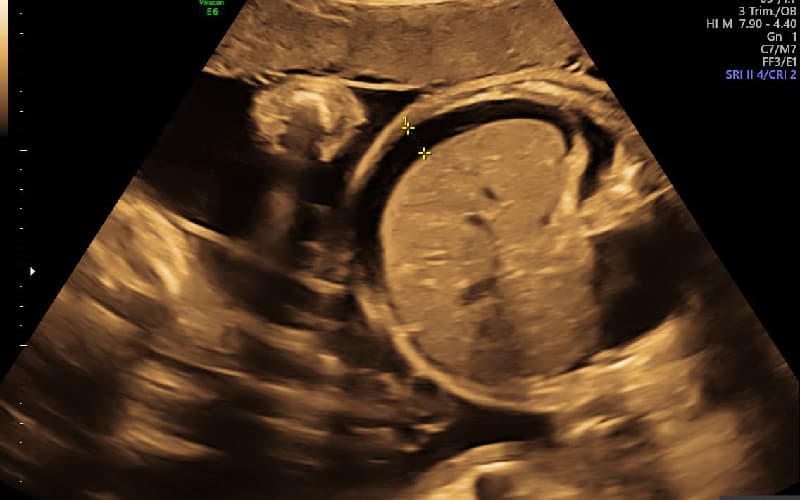

Bệnh lý này thường khó nhận biết qua các triệu chứng lâm sàng bên ngoài mà cần được chẩn đoán thông qua siêu âm thai định kỳ. Những dấu hiệu phù nhau thai phổ biến nhất là bệnh thường kèm theo tình trạng phù dây rốn và thai nhi cũng bị phù nề.